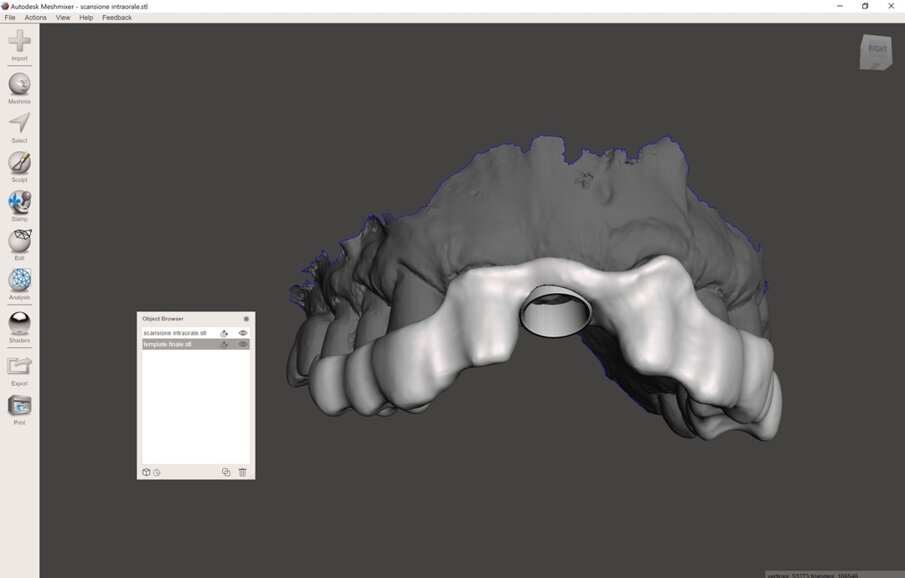

I dati Digital Imaging and Communication in Medicine (DICOM) derivanti dalla CBCT, insieme con il file standard tesselletion language (.STL) ottenuto tramite la scansione intraorale, venivano quindi caricati in cloud in un software di Intelligenza Artificiale (Virtual Patient Creator, RELU). Tali dati venivano elaborati e il software di Intelligenza Artificiale restituiva, in meno di 10 minuti, la ricostruzione 3D della maxilla del paziente, ottenuta tramite segmentazione ossea automatica, accoppiata e allineata alla scansione intraorale (Fig. 4). Il software, inoltre, restituiva la segmentazione di ciascun singolo elemento dentario, sotto forma di files .STL separati, nei quali la corona veniva direttamente dalla scansione intraorale, mentre la radice dalla CBCT (Fig. 5). La “fusione” automatica del dato della CBCT con quello della scansione intraorale, e il perfetto allineamento tra le strutture anatomiche, rappresentava il risultato dell’applicazione dell’Intelligenza Artificiale. La stessa area rigenerata veniva opportunamente segmentata (Fig. 6). A questo punto, l’operatore era in grado di visualizzare tutte le strutture, selezionare quelle interessanti ed esportarle come files .STL. Tali files venivano quindi caricati all’interno di una applicazione dedicata per l’uso per la realtà aumentata (Holodentist, Fifthingenium), insieme con la libreria implantare del sistema scelto (Naturactis, Lyra ETK) per la risoluzione dello specifico caso clinico (Fig. 7). L’operatore vestiva quindi gli occhialini per la Realtà Aumentata (MagicLeap2, Magic Leap) e, anche attraverso l’aiuto di uno specifico joypad, era in grado di pianificare l’impianto in 3D nell’esatta posizione, profondità ed inclinazione, impiegando gli ologrammi (Clicca QUI). Terminata la pianificazione e salvata la posizione dell’impianto, essa veniva esportata e impiegata per disegnare, all’interno di software open-source, un template per una chirurgia guidata statica (Figg. 8, 9). Dal momento che Intelligenza Artificiale e Realtà Aumentata non possiedono ancora le certificazioni per l’impiego clinico, tutti i files erano quindi re-importati all’interno di software radiologico certificato (MIMICS, Materialise) per il controllo della posizione implantare nelle cross-sections radiologiche (Figg. 10, 11).

Fig. 8_Disegno della dima chirurgica con software open-source (Meshmixer, Autodesk), visione occlusale.

Fig. 9_Disegno della dima chirurgica, visione prospettica.